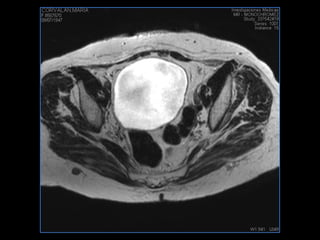

PROTOCOLO pelvis SAG T2, Y FAT SAT (FINOS) AXIAL T1  AX FAT SAT CON   GADOLINIO :  AX T1 Y COR T1 SAT: NO  FASE: RL THK: 3MM  COIL:  GAP: (FACTOR 1.4) 1MM FOV: 40 CM NEX:2 SINCRONIZACION RESPIRATORIA EN 3 O 4 CICLOS ALE

resonancia de abdomen